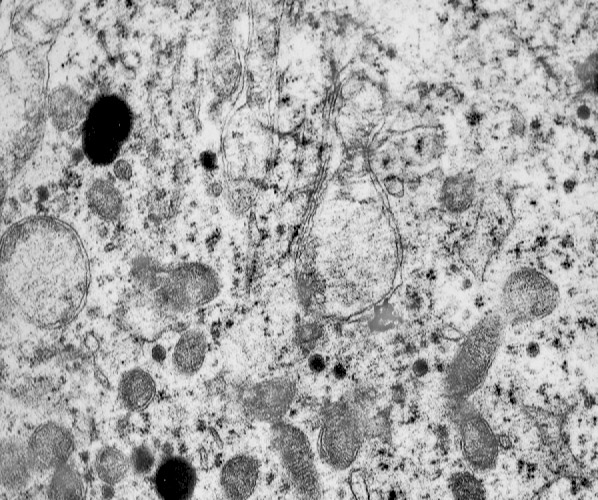

MICROAUTOFAGIA

I focolai di microautofagia si ritrovano frequentemente commisti a mitocondri disfunzionali e a reticolo- endoplasmatico in stato di stress.

Essi sono di piccole dimensioni, appaiono come vescicole, delimitate da una membrana a doppio strato, immerse nel citosol e

ricolme di materiale amorfo oppure di materiale amorfo commisto a frammenti filamentosi.

Fig.2